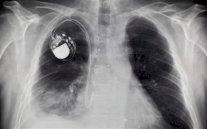

توصلت دراسة حديثة ضمت نحو ثلاثة آلاف شخص في هولندا إلى أن اليوغا ترتبط بصورة مستقلة بتراجع مستوى عوامل الإصابة بأمراض القلب مثل ارتفاع ضغط الدم وزيادة نسبة الكوليسترول.

ومقارنة بعدم ممارسة أي تمارين على الإطلاق، فإن اليوغا لها فوائد جمة، إذ أن لها علاقة بخفض مخاطر الإصابة بالبدانة وارتفاع ضغط الدم ونسبة الكوليسترول، بحسب الدورية الأوروبية لطب القلب الوقائي.